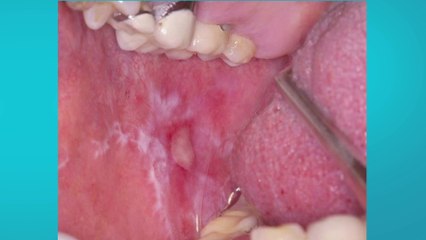

Dr. Jazmin Camacho ofrece consejos para detección temprana del cancer